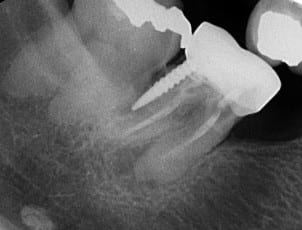

Finalement, séance suivante: mise en évidence d'un saignement dans le logement du tenon.

Obturation à la biodentine que j'ai fait "descendre dans le logement du tenon " avec un insert fin sans eau.

Disparition des symptômes la semaine suivante.

Contrôle à 6 mois, dent asymptomatique, radio encourageante.

voila

46perfbiod pzrftq - Eugenol